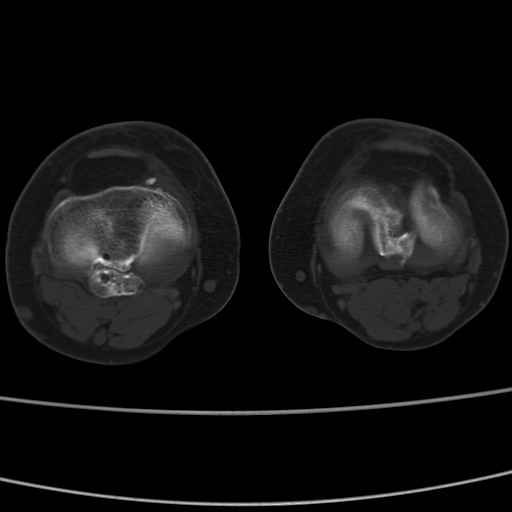

女性,50岁。【请提供患者临床症状体征】

右膝关节退行性改变,关节游离鼠。

右膝关节退行性改变,滑膜黏液囊钙/骨化并游离。

右膝关节退行性改变